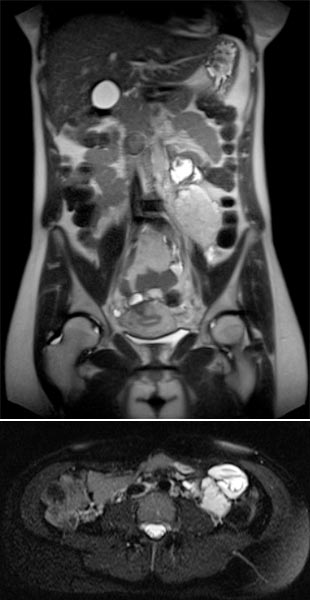

Koronare und axiale T2-gewichtete Haste-Sequenzen ohne Kontrastmittel 8 Wochen nach der Entbindung. Postpartal zeigt sich wieder eine deutliche Größenreduktion der venösen Malformation.

Die venöse Malformation zeigt 8 Wochen nach Entbindung bereits wieder eine deutliche Größenregredienz, sodass bei der stillenden Mutter aktuell keine minimalinvasive Behandlung mittels Sklerotherapie notwendig ist. Die große venöse Malformation war zu diesem Zeitpunkt auch asymptomatisch.